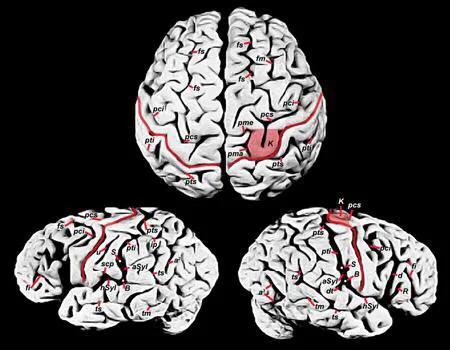

人类大脑区域图

(2)科学家进一步对其大脑进行解剖研究发现,爱因斯坦的大脑比普通人的大脑少了一块儿(盖区),这样就使得他大脑左右半球的顶下叶区域非常发达,是普通人不能比的,而且他的大脑宽度约超过正常人15%,而这将会使视觉空间认知数学思维和运动想象力方面发挥着重要作用。